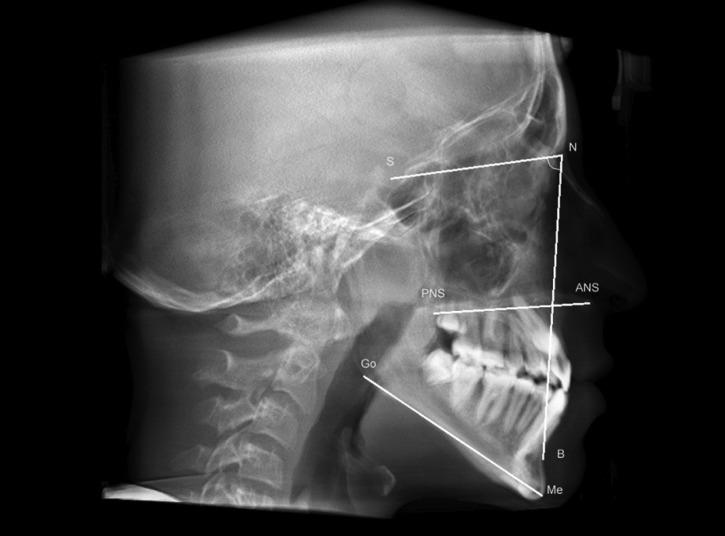

This study was conducted with 36 Brazilian individuals with NF1 with ages ranging from 4 to 75. The participants were submitted to anamnesis, extra and intraoral exam and cephalometric analysis using cone beam computed tomography. Height of the NF1 individuals was compared to the length of jaws and skull base. The results of the cephalometric measurements of the NF1 group were compared with a control group paired by age, gender and skin color.

Individuals with NF1 had lower maxillary length (p<0.0001), lower mandibular length (p<0.0001), lower skull base length (p<0.0001). In children and adolescents, the mandible was more posteriorly positioned (p=0.01), when compared with the control group. There was no association between jaws and skull base length with the height of the individuals with NF1.

Brazilian children, adolescents and adults with NF1 have short mandible, maxilla and skull base. Moreover, children and adolescents present mandibular retrusion.

本研究对36名年龄在4至75岁之间的巴西NF1患者进行。参与者接受了问诊、口腔内外检查,并使用锥形束计算机断层扫描进行头影测量分析。将NF1患者的身高与颌骨和颅底长度进行比较。将NF1组的头影测量结果与按年龄、性别和肤色配对的对照组进行比较。

NF1患者的上颌长度较短(p<0.0001),下颌长度较短(p<0.0001),颅底长度较短(p<0.0001)。与对照组相比,儿童和青少年的下颌位置更靠后(p=0.01)。NF1患者的颌骨和颅底长度与身高之间没有关联。

巴西NF1儿童、青少年和成人的下颌骨、上颌骨和颅底较短。此外,儿童和青少年存在下颌后缩。